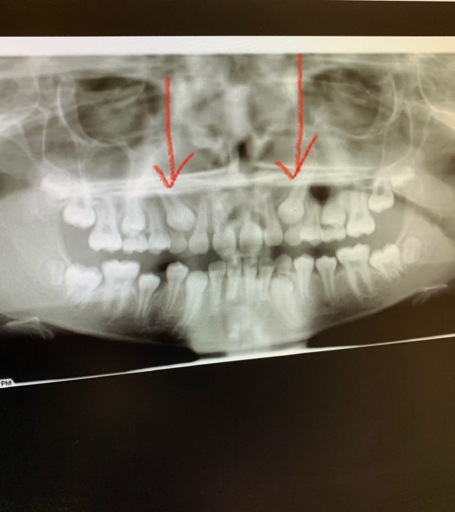

What is the procedure for impacted Canines that are at the top only for both canines and they are in the top of the gums on the outside (not in palette). I have an X-ray. ITS FOR MY DAUGHTER... 12 years old and 2 months.

Impacted Canines